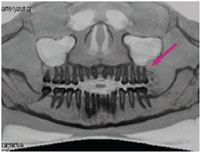

The patient expressed pain in the maxillary left third molar region and said she was able to drain the swollen area with digital pressure. An oral exam revealed an expansile purulent lesion approximately 14 mm in diameter superior and distal to the maxillary left third molar. A panoramic radiograph revealed a radiolucency superior and distal to #16 (Figure 9). The lesion appeared to be extending into the sinus.

Determining the cause of this radiolucency was difficult to ascertain on the panoramic X-ray, so CBCT scans were taken. The scans demonstrate the three planes with the window/leveling inverted to display the dental anatomy in greater detail (Figure 1 through Figure 3). The red arrows show the purulent lesion. These additional views clearly outline the cystic lesion in three different planes, as well as the reconstructed panoramic view. The data provided by the scans provide better orientation of the lesion to the surrounding anatomical structures.